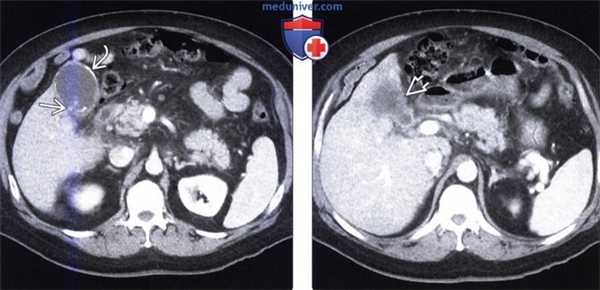

(Слева) На аксиальной КТ с контрастным усилением определяется частичное обызвествление стенки желчного пузыря. Обратите внимание на плохо различимое образование мягкотканной плотности в просвете желчного пузыря и нечеткую границу с прилежащими отделами печени.

(Справа) На аксиальной КТ с контрастным усилением визуализируется дискретное объемное образование в желчном пузыре («классическая» картина рака желчного пузыря). Для рака желчного пузыря более типичным является ограниченное, а не диффузное обызвествление стенки.